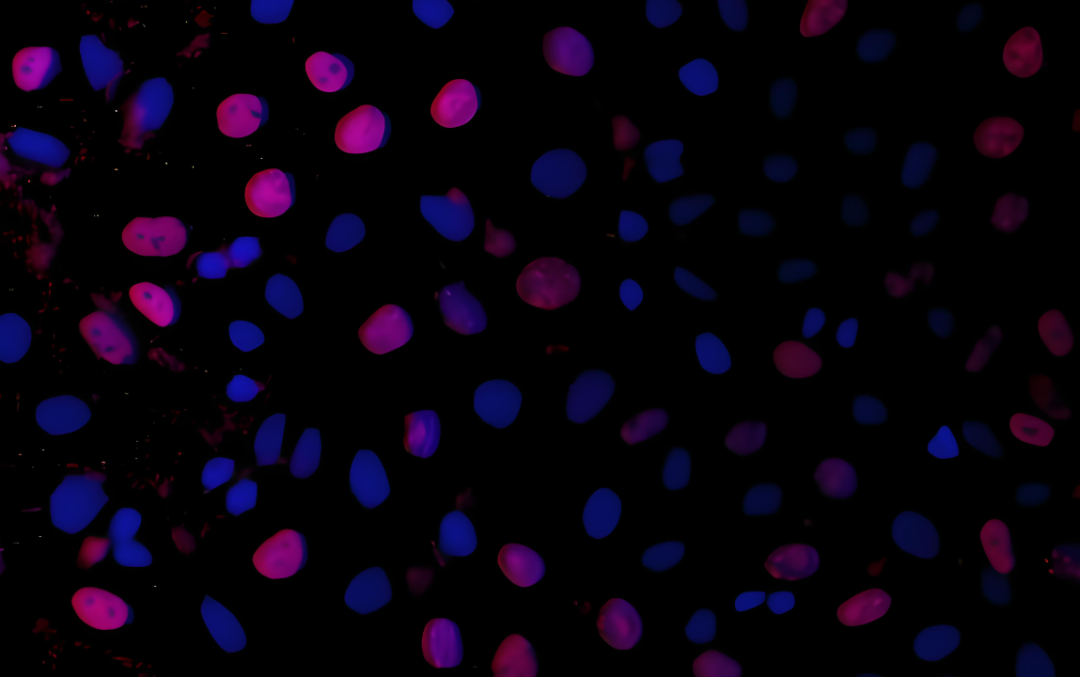

显微成像技术在医学中至关重要,能够在细胞和分子水平上分析生物结构,帮助诊断疾病。然而,对显微图像的手动分类效率低下,且需要大量专业知识。虽然 CNN 能有效提取局部特征,但其捕捉长距离依赖关系的能力有限;ViT 虽能建模全局依赖关系,但计算复杂度高。

研究人员用五个公共医学图像数据集对 Microscopic-Mamba 模型进行了广泛的测试,均表现出了优异的性能。

这些数据集包括视网膜色素上皮 (RPE) 细胞数据集、用于疟疾细胞分类的 SARS 数据集、用于结直肠息肉分类的 MHIST 数据集、用于肿瘤组织分类的 MedFM…